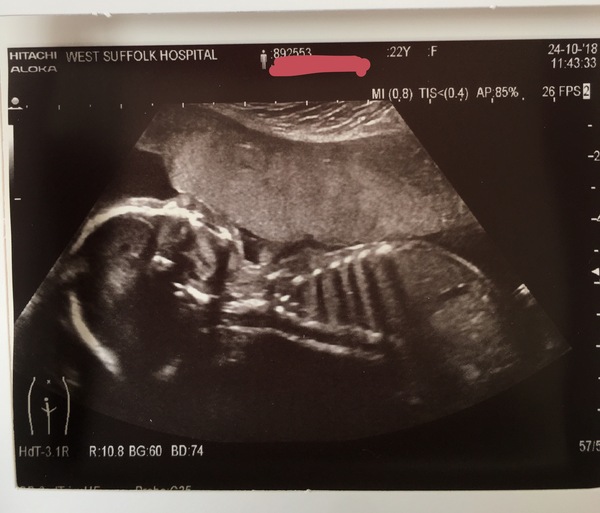

CobaltRose96 · 24/10/2018 13:45

Scan today confirmed a healthy baby girl ❤ Absolutely thrilled!

She was being a monkey though and had her face wedged against the placenta, making it hard to get a decent profile shot Grin

Congratulation @CobaltRose96 that picture is amazing!